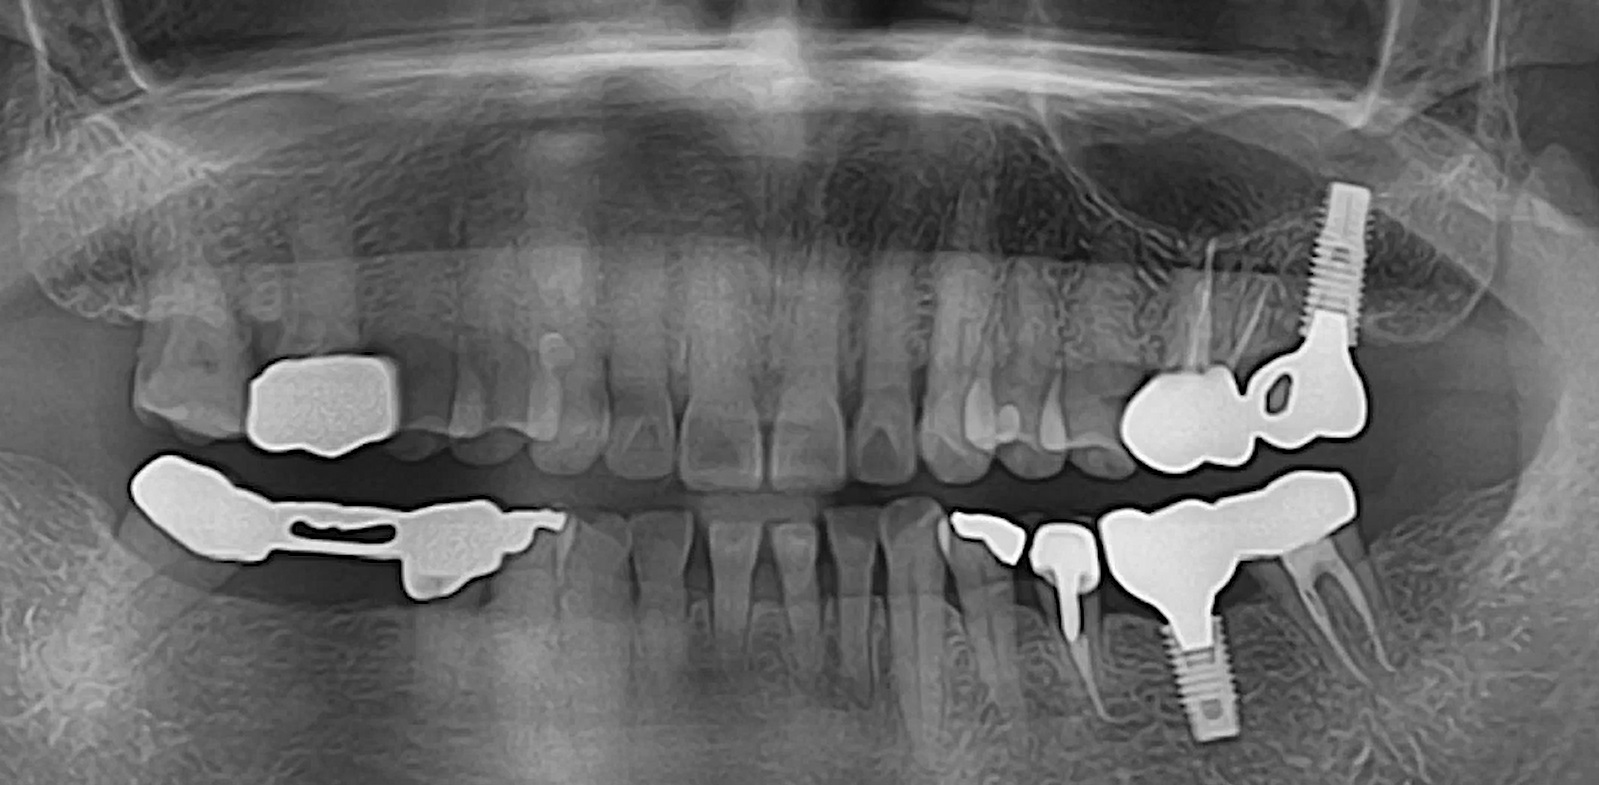

R2GATE Guide Surgery with MiNi

Dr. Kwang Bum Park,Immediate loading,Digital Guided Surgery,Maxillary Anterior,#12,Guided surgery,Immediate Placement,Flapless,MiNi,R2GATE Guide,MEG-TORQ,MEGA ISQ,Video